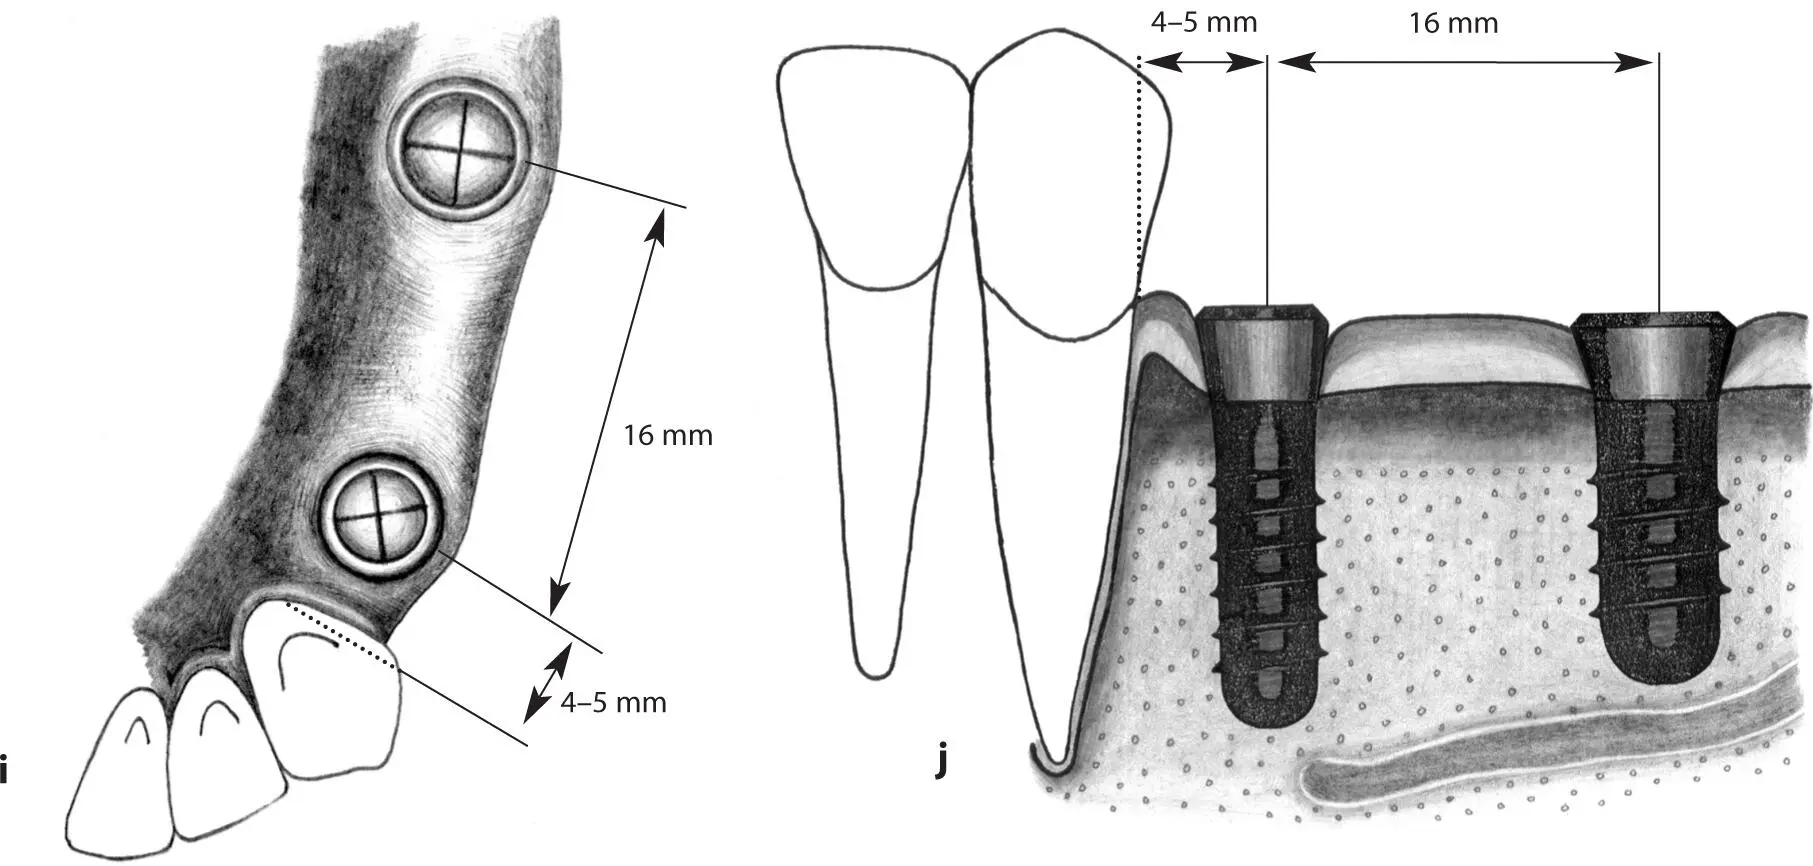

Figs 1-11i and 1-11j Occlusal (i) and lateral (j) views of implants positioned in the first premolar and first molar sites. In this extended posterior distal extension situation, a regular neck implant and a wide neck implant are indicated as abutments for a three-unit fixed partial denture. The regular neck implant is positioned 4 to 5 mm from the tooth. The wide neck implant is inserted about 16 mm from the anterior implant.

Figs 1-11k and 1-11l Occlusal (k) and lateral (l) views of a short distal extension situation. A regular neck implant is indicated to restore the missing first molar and serve as a distal abutment to a combined tooth- and implant-supported three-unit fixed partial denture. The implant is positioned 11 to 12 mm from the tooth.